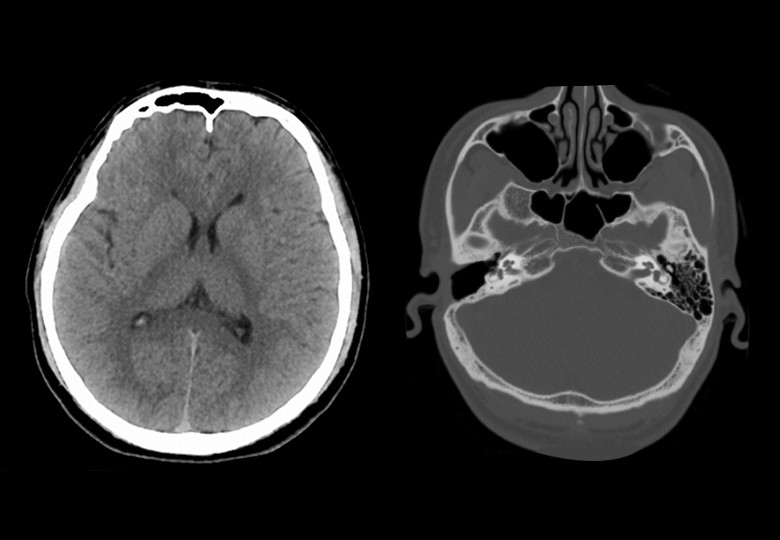

Head Scan